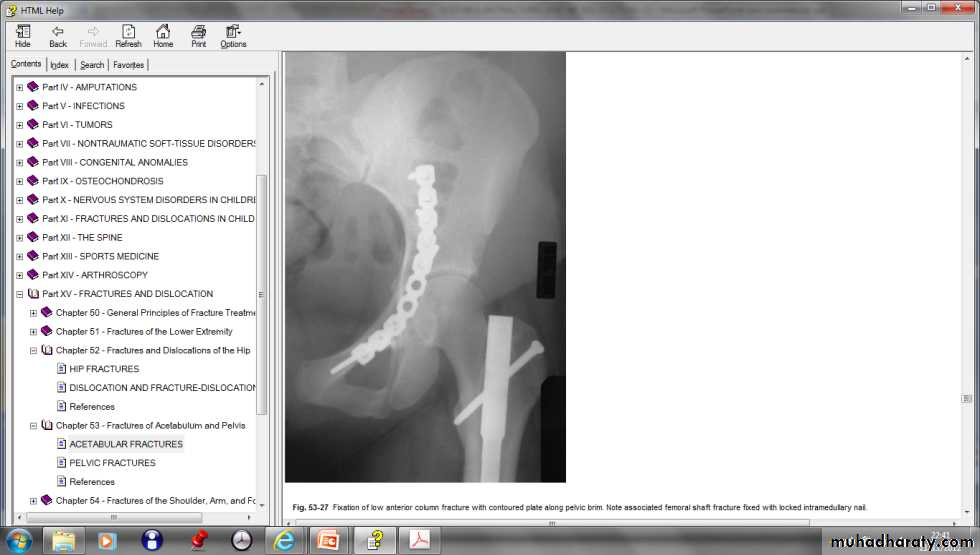

The first priority is to counteracthe shock and reduce a dislocation. Skeletal traction is then applied to the distal femur (10 Kg). During the next 3–4 days the patient’s general condition is brought under control. Definitive treatment of the fracture is delayed until the patient is fit and operation facilities are optimal.Definitive treatment:

undisplaced fractures and fractures that do not involve the roof ( weight bearing portion), skeletal traction is applied for 6-8 weeks , followed by non weight bearing for other 6 weeks. Operative treatment are indicated for all displaced fractures to get perfect anatomical reduction.